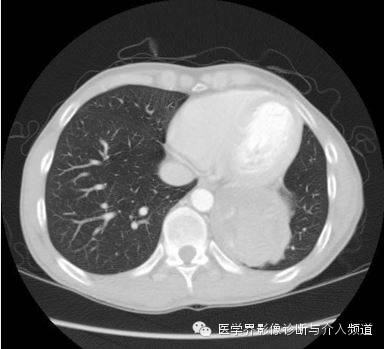

胸片示左下胸腔一肿块影。CT增强示左肺下叶一低密度肿块,其内可见高密度影,PET-CT示肿块边缘FDG摄取增加,肿块中央摄取减低。

异物性肉芽肿是纱布在人体内出现周围肉芽组织增生、纤维化时所形成的肿块,CT 表现为不均匀混杂密度软组织影,壁较厚,增强后壁由于含大量纤维结缔组织而呈明显强化,其内容物无强化。

异物性囊肿或脓肿是由于纱布引起的周围组织 、器官的慢性炎性反应,出现渗出、液化坏死并纤维包裹所形成的囊肿或脓肿,周围有假性纤维包膜或较厚的壁,CT 表现为囊性为主的混杂密度块影,壁较光滑,其内出现云雾状、漩涡状或脑回状密度增高影漂浮于其中,增强后亦表现为壁强化,内容物无强化。部分学者报道,纱布瘤内部出现气泡及边缘出现钙化是其重要特征之一。

综上所述,发生于胸腔或腹腔的肿块,具有良性病变的实性或囊性占位特征,肿块内部可见云雾状或漩涡状稍高密度影,可以出现边缘钙化,增强后壁强化,内容物无强化,再结合患者既往有手术病史,应首先考虑腹腔或胸腔纱布瘤。